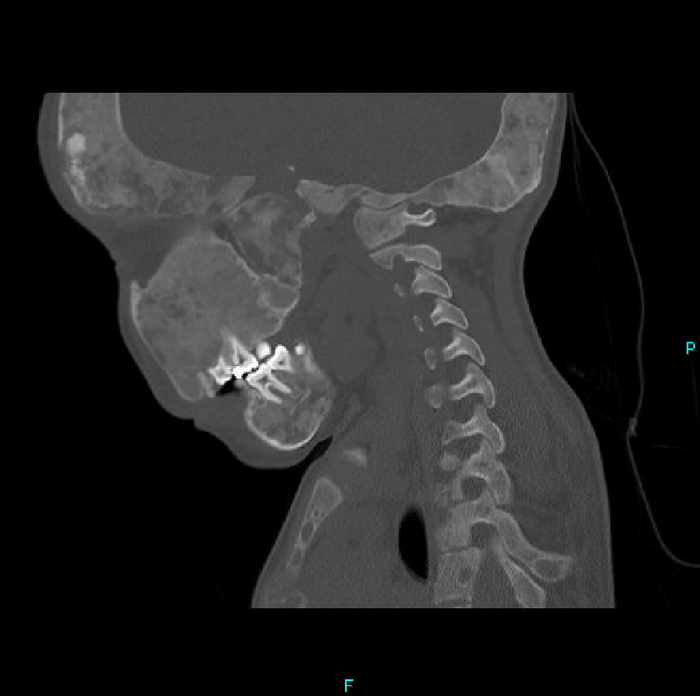

Но вернёмся к случаю: Пациент - девочка, 15 лет. Поступила после ДТП. У нас было проведено КТ-обследование по протоколу политравмы (голова / шея / грудь / живот / таз), где свежих переломов обнаружено не было, но были непонятные леденцы с костями, а именно структура и форма костей со следами старых переломов (грудная клетка и таз с бедренными костями) и, как следствие, их деформацией + следы проведённого остеосинтеза (операция с последующей фиксацией кости тем или иным способом) обоих бедренных костей. Сегодня без пометок / стрелочек, так как картинки говорят сами за себя (всё в костном окне, и всё, что мы видим - кости):

Структура костей напоминала таковую при фиброзной дисплазии (аномалия развития костной ткани с замещением нормальной кости фиброзной тканью, не является опухолью), но, обычно, эти диcплазии возникают в одном месте, т.е. поражают 1 кость (моностотическая форма) и, намного реже, бывают множественные поражения (полистотическая форма), но не всего скелета, как в нашем случае.